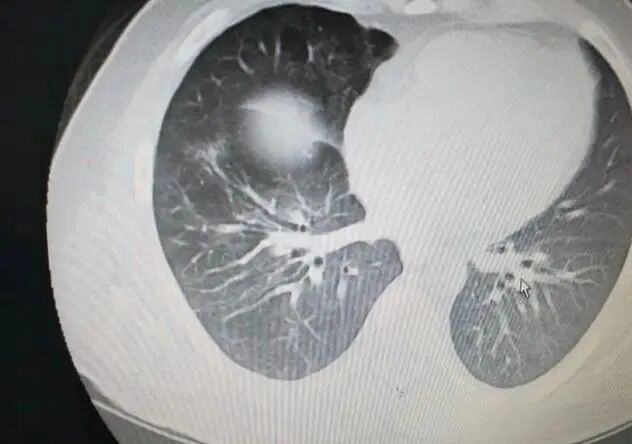

医生一看老李的手,就发现了问题,那手指头跟杵状指似的,医生就怀疑是肺部有问题。结果一检查,可不得了,老李竟然得了肺癌!

老李一听这消息,简直不敢相信自己的耳朵,他一直在想:“我都不抽烟,这肺癌怎么会找上我呢?”好在癌细胞还没转移,老李赶紧做了手术,现在身体恢复得还不错,双腿也不那么疼了。